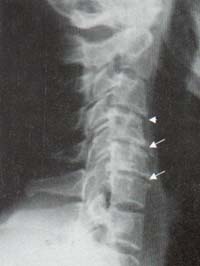

Se observa una placa osificada de espesor variable a lo largo de la columna cervical más frecuentemente de C3 a C5. Frecuentemente está separada del cuerpo por una delgada zona radiolúcida, los discos intervertebrales en el área comprometida se encuentran preservados. La placa calcificada usualmente mide de 1 a 5 mm de grosor, puede star presente en una o varias vértebras.

En la columna torácica pueden observarse estos hallazgos entre la 4 y la 7 vértebra16-17. El compromiso de la columna lumbar se puede presentar a cualquier nivel. Puede haber coexixtencia con DISH (Figura 15)18.

Figura 18. Columna cervical. Osteofitos formando puentes entre C4-C5, C5-C6 (Flechas). Osteofito incipiente en C3 (Cabeza de flecha).